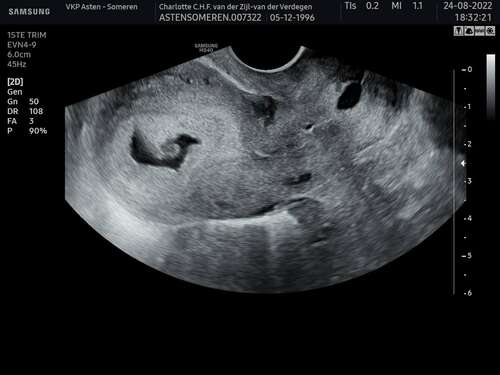

Iemand een idee wat die zwarte vlek links zou kunnen zijn ?

Het lijkt toch echt op de zwarte vlek die ik ook had. De echo die ik na de echo met de vlek had was de vlek gewoon weg dus denk niet dat je je echt zorgen hoeft te maken ❤️